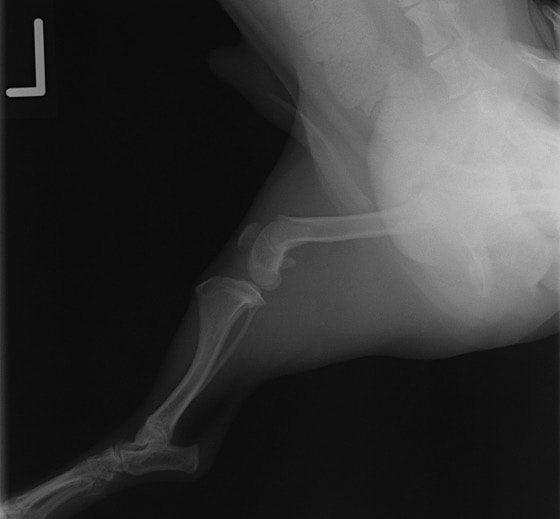

症例3:キルシュナーワイヤーのピンニングによる整復

ペルシャ猫 11ヶ月齢 雄

他院にて左大腿骨遠位の成長板骨折(salter-harrisⅠ型)が認められており、治療相談を目的として来院。当院にて、キルシュナーワイヤーを用いたピンニングにより骨折部位の整復を行いました。術後の経過は良好で、現在も経過観察中です。

術前レントゲン

術後レントゲン